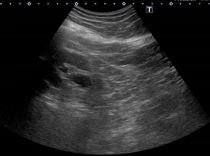

膀胱エコー

膀胱エコー残尿多量な状態

残尿多量な状態

神経因性膀胱が長期にわたり続いた結果、膀胱尿管逆流症を併発し両側水腎症(腎臓に尿がたまっている状態)を合併しています。この状態が長期間続くと腎機能の増悪に至ります。

写真の症例は、内科で過活動膀胱の薬を処方されている状態でした。

困ったことに、神経因性膀胱の患者さんは、尿意も鈍化しており残尿多量な状態に気づかない患者さんも多いです。